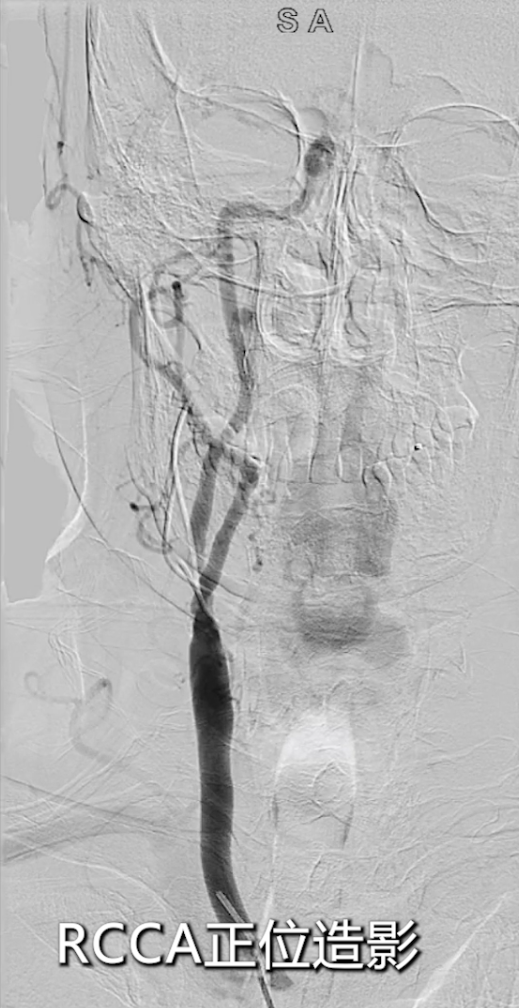

★ 病变评估

左侧颈总动脉造影:明确左侧颈内动脉闭塞,侧支循环通过颈外动脉部分供应颅内血流;

右侧颈总动脉造影(正位、汤氏位、侧位):明确右侧颈内动脉重度狭窄,病变远端直径5mm、近端直径8mm,长度约30mm,远端锚定区条件理想。